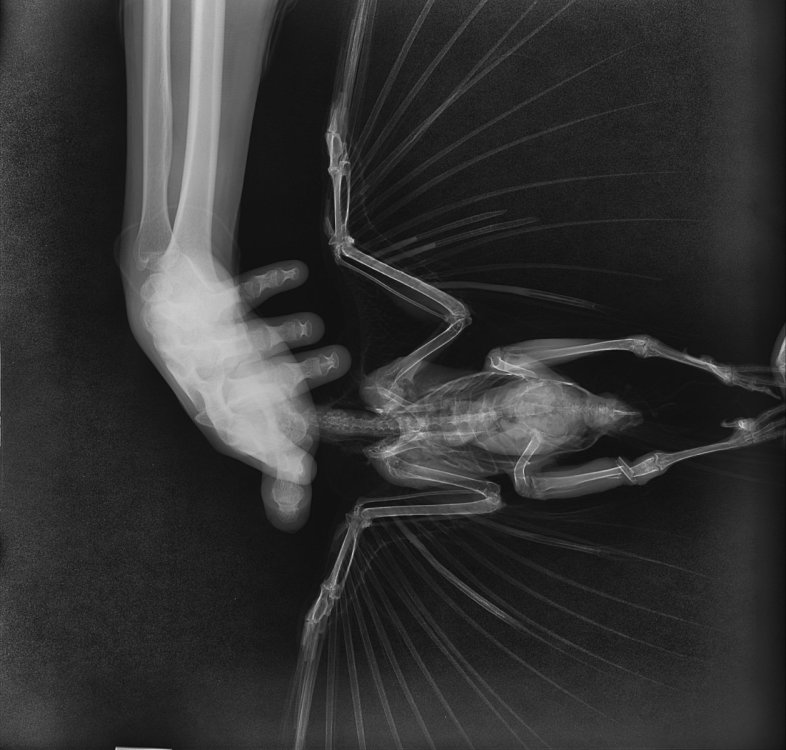

2. Перелом открытый, как выглядит (фото)?

IMG_1273.jpeg

IMG_1272.jpeg

У меня остаются подозрения, что где-то есть открытая рана, личинки не могут быть просто так. По рентгену не вижу, где могла бы быть. Лучше обратиться к Zosia, чтобы посмотрела рентген, быстрее будет по Вацапу в ее профиле.